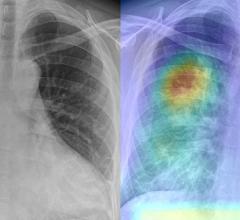

There has been a change in attitudes about AI on the expo floor at the Radiological Society of North America (RSNA) over the last two years. AI conversations were originally 101 level and discussed how AI technology could be trained to sort photos of dogs and cats. However, in 2020, with numerous FDA approvals for various AI applications, the conversations at RSNA, and industry wide, have shifted to that of accepting the validity of AI. Radiologists now want to discuss how a specific AI algorithm is going to help them save time, make more accurate diagnoses and make them more efficient.

With a higher level of maturity in AI and the technology seeing wider adoption, radiologists using it say AI gives them additional confidence in their diagnoses, and can even help readers who may not be deep experts in the exam type they are being asked to read.

There are now hundreds of AI applications that do a wide variety of analysis, from data analytics, image reconstruction, disease and anatomy identification, automating measurements and advanced visualization. The AI applications can be divided into 2 basic types — AI to improve workflow, and AI for clinical decision support, such as diagnostic aids.